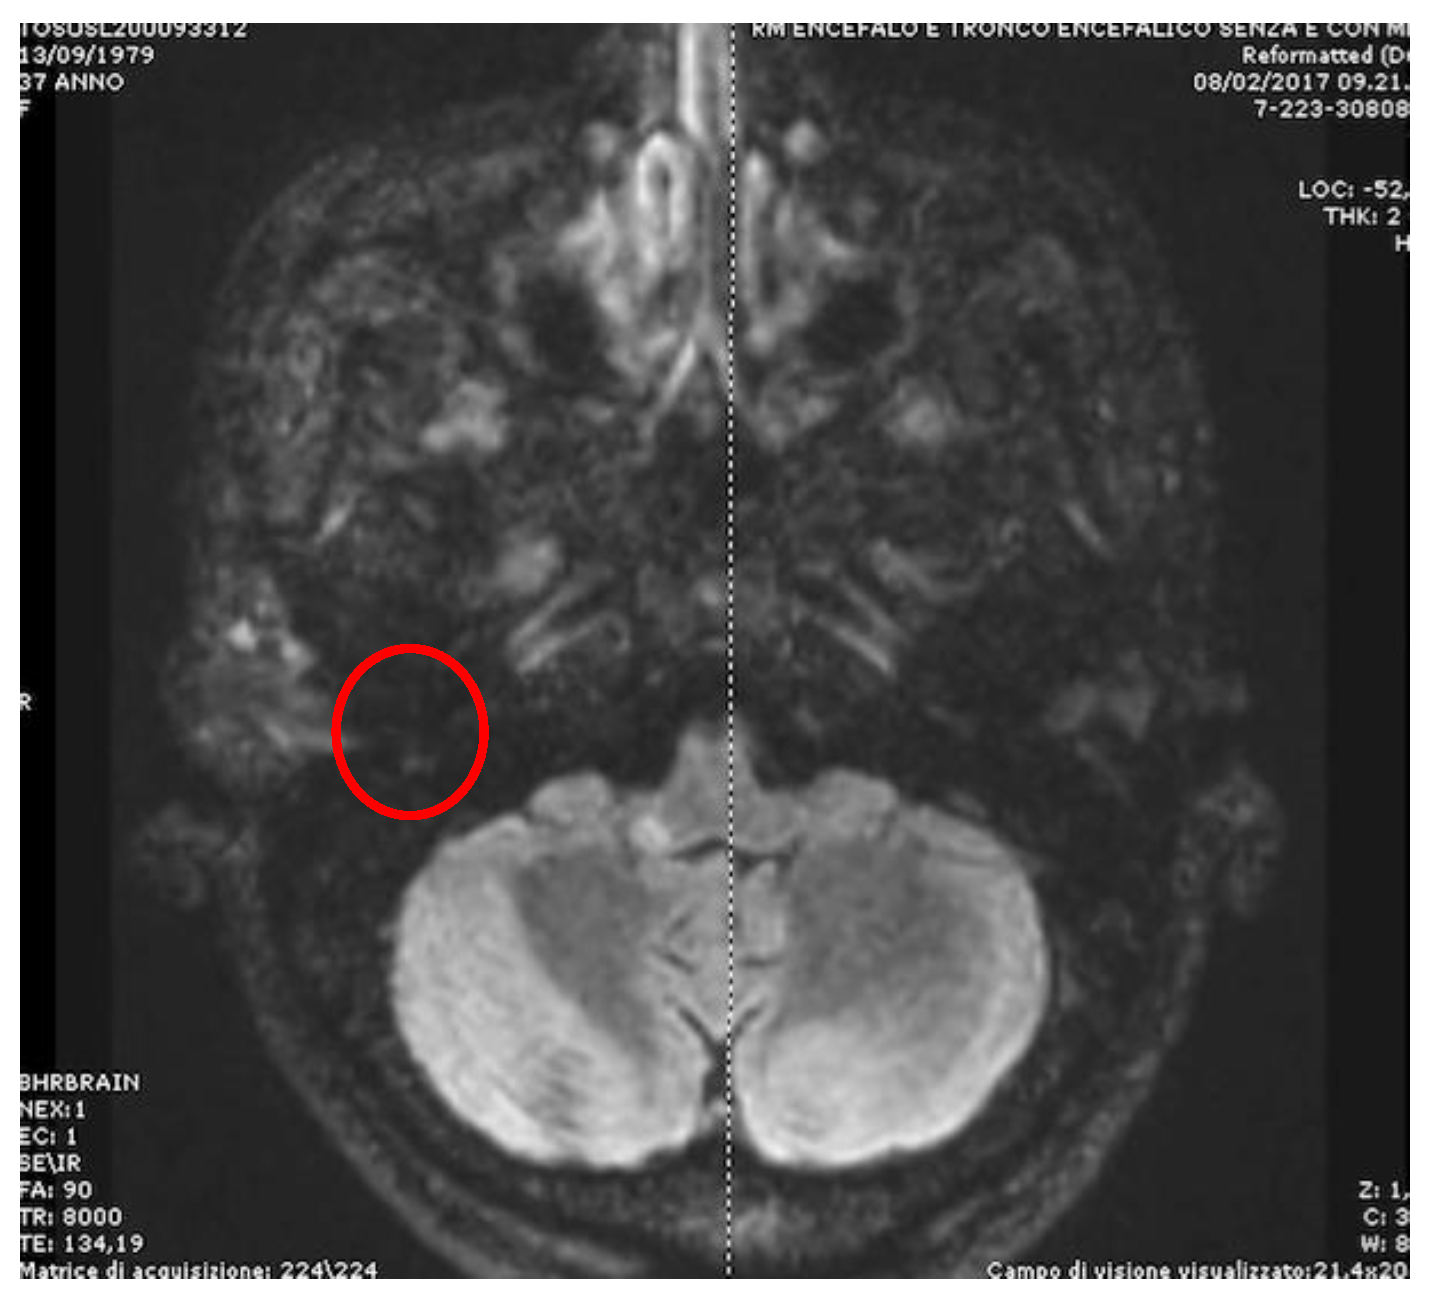

- Apogeotropic bidirectional horizontal nystagmus. More commonly associated with cerebellar disease [54], this type of CPN shows no latency and no associated vertigo, lasts as long as the position is maintained and is reproduced by returning the patient to the same position. A brainstem lesion could induce an apogeotropic CPN because of a damage of the connection from nodulus, uvula (and sometimes tonsil) to the vestibular nuclei [12,53,55] (Figure 4).